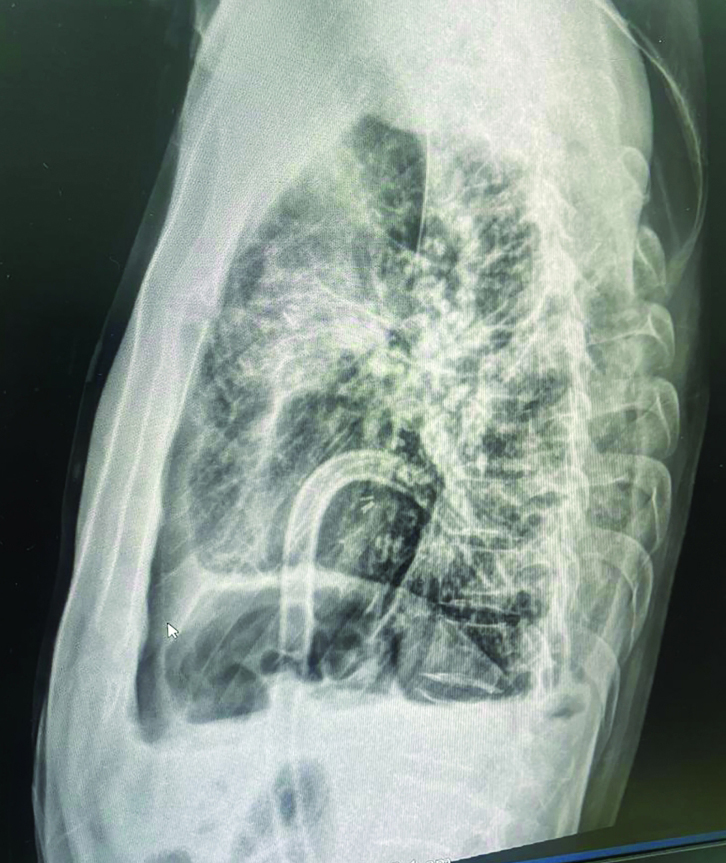

جهاز الأوكسجين يلازم المريض على مدار اليوم. من المصدر

يعاني «أبوياسين - مصري»، البالغ من العمر 44 عاماً، الإصابة بفشل رئوي حاد، اضطره إلى ملازمة جهاز الأوكسجين.

وروى «أبوياسين» لـ«الإمارات اليوم»، أن معاناته مع المرض بدأت عام 2013، إذ عانى وجود تليف بسيط في الرئة، وكان علاجه قاصراً على تناول الأدوية، لكن حالته بدأت تزداد سوءاً يوماً بعد الآخر، فيما كان التليف يزداد ومساحته تتسع.

وقال إن الأدوية التي كان يتناولها تضمنت الكورتيزون، مضيفاً: «بعد فترة، توقف الجزء الأيسر من الرئة، وأصبحت أعيش على رئة واحدة، ودخلت إلى وحدة العناية المركزة في مدينة الشيخ خليفة بن زايد الطبية، حيث رقدت لفترة تحت الملاحظة الطبية».

وأضاف المريض: «قبل نحو عام، تعرضت لحادث مروري وتضررت الرئة اليمنى، وبدأت تضعف، إلى أن فقدت قدرتها على العمل، وحالياً أعيش على جهاز الأوكسجين على مدار اليوم، ولا أستطيع الاستغناء عنه».

وقال: «دخلت إلى مستشفى كليفلاند في أبوظبي، وبعد إجراء الفحوص والتحاليل والمعاينة الطبية لي، تبيّن أنني أحتاج إلى زراعة رئة، باعتباري وصلت إلى مرحلة الفشل الرئوي».